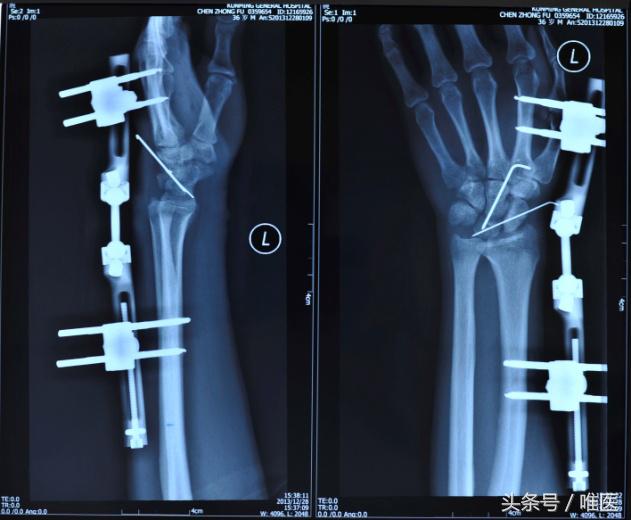

3.带关节外固定支架

Majeed曾报道对骨折脱位后的舟骨进行复位后选择合适加压螺钉固定后,用带关节的腕关节外固定架,分别于桡骨中远端及第2或3掌骨上各打入两枚合适粗度、长度的半针后连接外固定架后将其逐渐撑起,并锁紧固定半针及外固定架关节处,以防止其再次脱位。Driscol等认为利用外固定架独特的支撑作用,缓解腕关节内压力,维持正常间隙,对已切开复位固定的腕关节起到制动并减压作用,待3-5天之后,可松开外固定架的关节,但要保持其撑开状态,适当功能锻炼,减轻了关节面之间的摩擦,减少了肌肉软组织的挛缩及关节僵直等。